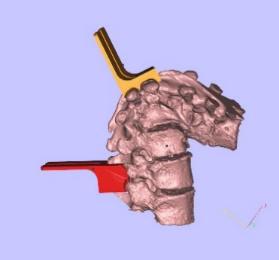

案例中病人的腰部脊柱發生嚴重畸形,進而影響神經系統,急需進行脊柱矯形術,恢復正常的脊柱形態。

需要實際觀察脊柱形態,以供醫生提前熟悉。根據手術方案定制手術截骨導板以及對應的植入物。

畸形的脊柱 手術方案

根據手術方案中的脊柱形態進行測量,定制個性化的假體和截骨導板。

需要截骨的平面 截骨導板放置位置

將脊柱模型添加支撐,把模型及導板3D打印出實物。

術前指導模型及截骨導板